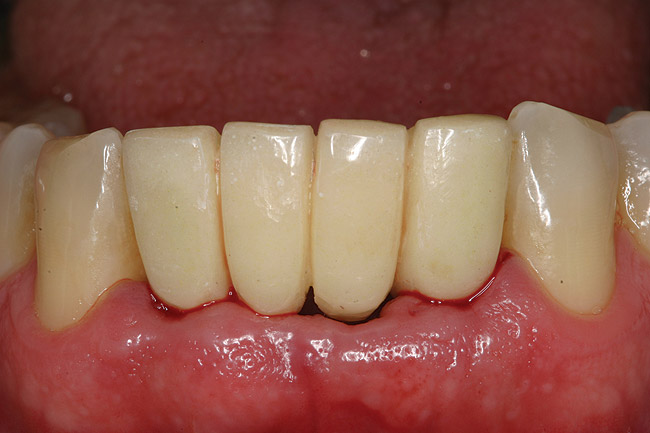

Figure 7b  Clinical healing completed.

Figure 7b

Figure 8  Final ceramo-metal restoration.

Figure 8

The patient was given postoperative instructions and advised to maintain a soft diet for 6 to 8 weeks to protect the implants. The patient was followed weekly for the first 3 weeks and monthly thereafter. After 4 months of healing, the provisional restoration was removed and the soft tissues were examined. Mature, keratinized gingival tissues were present facially, lingually, and interproximally. Nonkeratinized tissue could be seen at the tissue surfaces of the ovate pontics and in the intrasulcular regions of the implant abutment units. No clinical probing depths beyond 1 mm were found adjacent to the abutments. The healed tissue represented an acceptable clinical result especially in light of the gap that had been present at the time of implant placement (Figure 7A and Figure 7B). Final impressions were made, and the permanent ceramo-metal screw-retained prosthesis was placed within 8 weeks (Figure 8).

This patient has been followed for 4 years with no complications and no discernable clinical changes in soft- or hard-tissue levels.